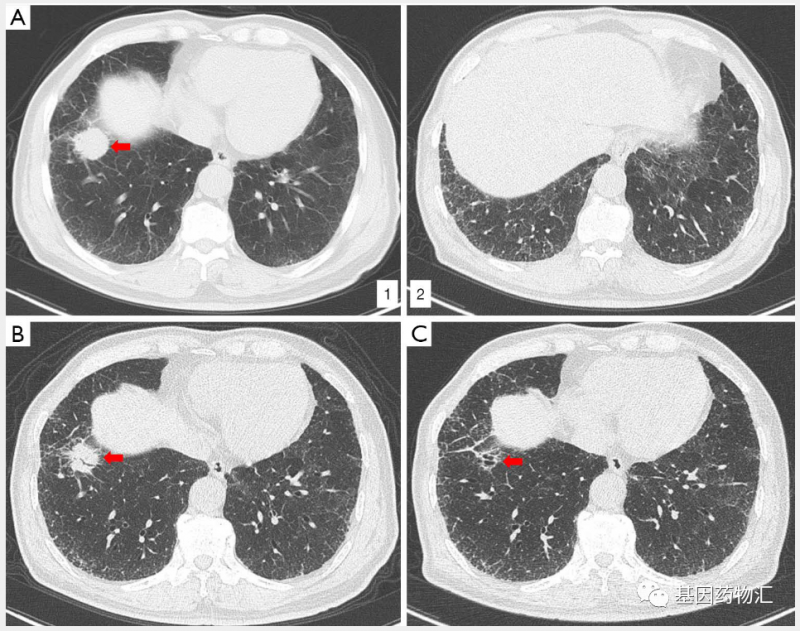

(A1)确诊时原发病灶;(A2)双侧肺间质性肺病;(B)治疗2个周期后,原发病灶缩小;(C)治疗4个周期后,原发病灶已经消失